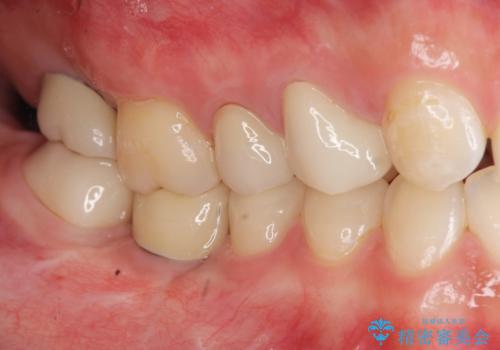

インプラントを用いた臼歯部欠損補綴

- 上下1本づつの歯を失い、噛めないことの改善を求めて来院されました。

保存可能な歯の虫歯・根管治療を行い、喪失した部分はインプラントを埋入、オールセラミックジルコニアクラウンを製作し審美的に仕上げていきます。